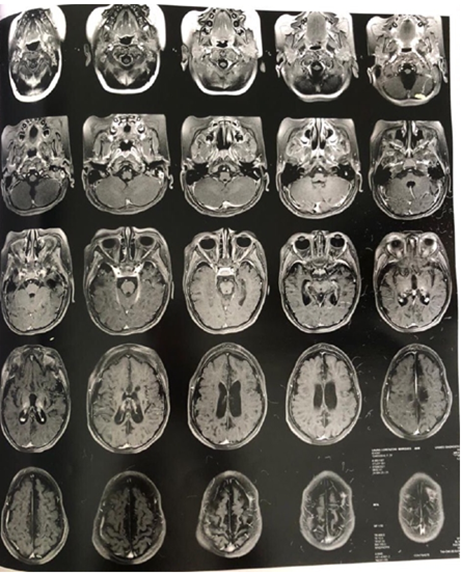

Neuroimaging: MRI (Figure-2) showed encephalomalacia and gliosis in the left parietal and occipital lobes with compensatory dilatation of the ipsilateral lateral ventricle. No cortical malformations or posterior fossa abnormalities.

Figure-2A: MRI showed encephalomalacia and gliosis in the left parietal and occipital lobes

Figure-2B: MRI showed encephalomalacia and gliosis in the left parietal and occipital lobes

Figure-2C: MRI showed encephalomalacia and gliosis in the left parietal and occipital lobes

Figure-2D: MRI showed encephalomalacia and gliosis in the left parietal and occipital lobes

Figure-2E: MRI showed encephalomalacia and gliosis in the left parietal and occipital lobes